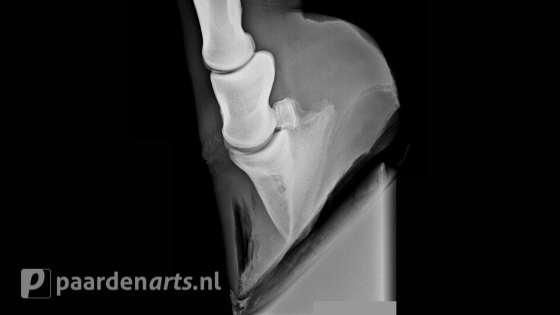

Bij verdenking op hoefbevangenheid zal de dierenarts direct moeten worden ingeschakeld. Deze zal allereerst enkele klinische testjes uitvoeren om te bepalen waar het paard precies pijn heeft. Vervolgens is het van belang dat er bij werkelijke hoefbevangenheid röntgenfoto’s worden gemaakt om het stadium van de hoornwand/hoefbeenverhouding te bepalen en een behandelplan vast te stellen. Medicijnen worden voorgeschreven (indien nodig) om de pijn te verlichten en de ontsteking te remmen. De dierenarts zal tevens de oorzaak willen opsporen om zo verergering te voorkomen, hiervoor is vaak bloedonderzoek noodzakelijk. Daarnaast is een goed voederadvies erg belangrijk. Hoefbevangen paarden moeten sober gevoerd worden en omdat zelfs de suikers uit een klein beetje gras al schadelijk kunnen zijn, mogen zij niet op de wei, ook niet als er slechts weinig gras in staat. Een paddock met zand daarentegen is prima. Ook een natte paddock is goed want dan worden de hoeven van het paard direct gekoeld. Zorg wel altijd voor een droge plek waar het paard of de pony kan gaan liggen.